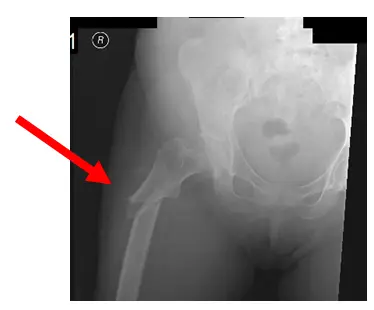

Dans ce cas, la fracture du patient est « béante », comme le montre la flèche. Il n’y a pas non plus de renouvellement osseux, ce qui peut conduire au « syndrome des os gelés », ce qui rend cette fracture particulière difficile à guérir. Pour le traitement de la fracture, le patient a subi une fixation interne à réduction ouverte (ORIF) avec augmentation, en utilisant des protéines morphogéniques osseuses.

La radiographie montre une fracture sous-trochantérienne oblique du fémur droit avec angulation latérale.